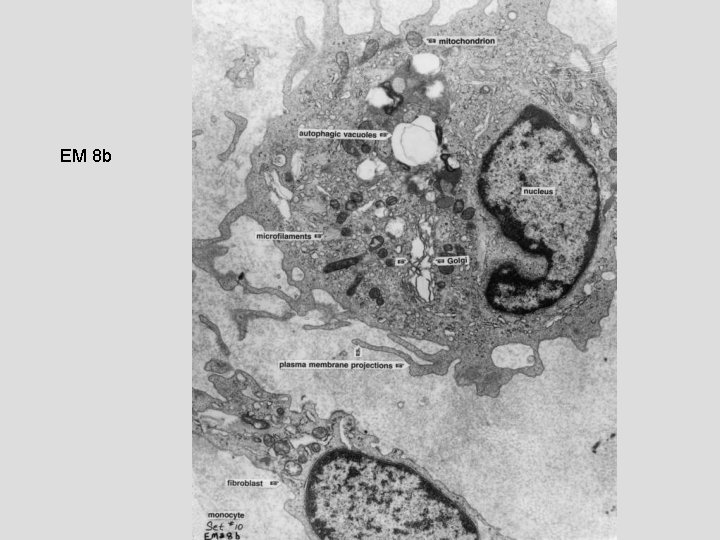

EM 8 b